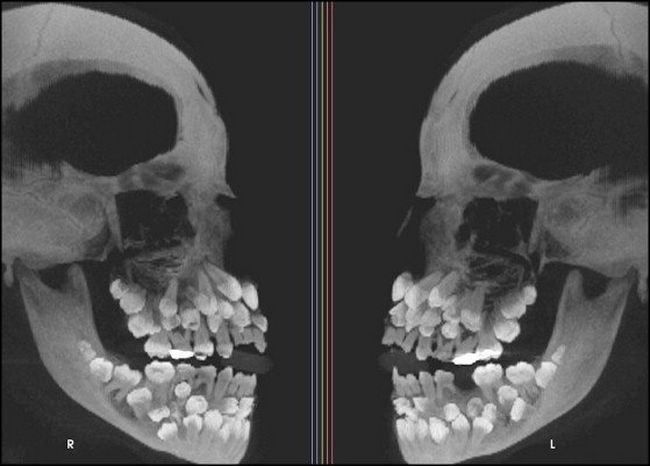

3 – Raio X de uma pessoa com hiperdontia